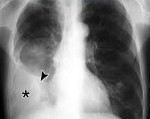

Осумкованный плеврит

Осумкованный плеврит – локальное скопление экссудата, ограниченное плевральными сращениями от остальной плевральной полости. В зависимости от локализации и объема экссудата клиническая картина варьирует от бессимптомного течения до выраженных проявлений,...